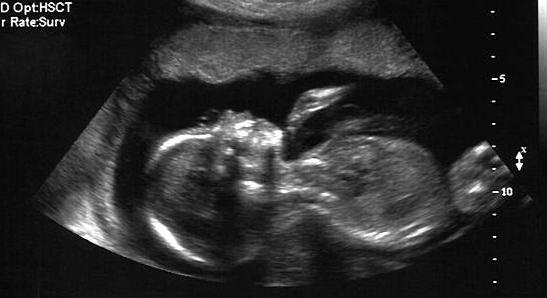

Les mesures exceptionnelles mises en place dès le premier confinement pour assouplir les conditions des IVG médicamenteuses à domicile sont pérennes depuis la parution d’un décret au Journal officiel du 20 février 2022.

Ainsi, le recours à la téléconsultation avec un praticien autorisé (médecin ou sage-femme conventionnée) reste autorisé. Les médicaments nécessaires à l’interruption volontaire de grossesse sont délivrés en officine, directement à la patiente, après réception de la prescription via une messagerie sécurisée (la pharmacie doit être désignée par la patiente lors de la consultation).

Enfin, l’allongement du délai d’accès à l’IVG a été confirmé à 9 semaines d’aménorrhée (7 semaines de grossesse), contre 7 semaines avant la crise sanitaire.